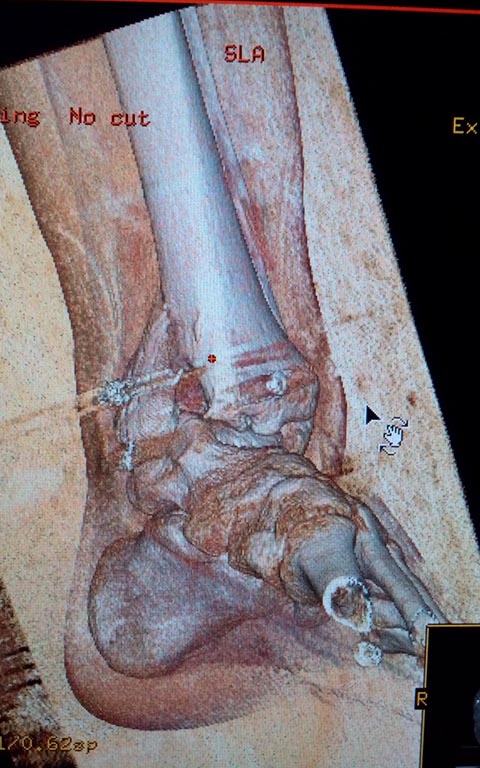

Мужчина, 1987 г.р. получил травму 10.2014. ДТП. Закрытый двухлодыжечный перелом костей костей левой голени, перелом заднего края большеберцовой кости с подвывихом стопы кзади, кнаружи.

Наложен дистрактор. Операция 10.2014: закрытая репозиция, остеосинтез спицами, винтами. В дальнейшем произошло ожидаемое усугубление нарушений взаимоотношений в голеностопном суставе.

Какой план лечения,на Ваш взгляд, предпочтительнее в данном случае? Возможно ли одномоментно устранить подвывих или только на аппарате Иллизарова? Первичные снимки после травмы отсутствуют. Критично ли "растоптана" латеральная суставная поверхность большеберцовой кости?

Мне кажется, что вопрос, поставленный Вами: "Возможно ли одномоментно устранить подвывих или только на аппарате Иллизарова?", отражает не совсем ясное понимание ситуации. Что значит устранить подвывих? А пластику ложных суставов внутренней лодыжки и заднего края большеберцовой кости не нужно делать? И ось голеностопного сустава нужно исправлять. То есть делать остеотомию наружной лодыжки (если она срослась, по снимку не очень понял). Артродез голеностопного сустава в такой ситуации очень сложен. Если же добиться сращения всех переломов в правильном положении, артродез вполне можно отсрочить на несколько лет, что для молодого пациента достаточно важно. Но в конечном счете все определяется Вашим умением и ясным представлением того, чего Вы хотите добиться своей операцией. Во вложении - в чем-то похожий случай. Оперировал эту пациентку 23 лет 11 лет назад через 8 месяцев после похожего на представленный Вами остеосинтез. На первой операции перелом малоберцовой кости в нижней трети был просто не замечен. За счет восстановления оси быстро развившийся артроз протекал благоприятно. В результате артродез был выполнен только в прошлом году, через 10 лет после второй операции. И боли беспокоили пациентку только в течение года перед артродезом.